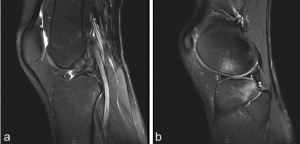

A 28-year-old female presented to our institution with left knee pain and instability for 6 weeks. Before pain onset, the patient sustained a fall while skiing. She reported feeling two pops in her knee upon falling. Her pain was associated with weakness and persisted at rest. Physical examination of the left knee revealed mild effusion with tenderness at the anterior knee joint. The Lachman test was positive with a grade 2 score. She was stable to varus and valgus stress tests. Dial test was negative. She had full range of motion with a mild antalgic gait. Perioperative magnetic resonance imaging (MRI) demonstrated a full-thickness ACL tear with a typical bone bruise pattern (Fig. 1).

Figure 1: (a) Sagittal magnetic resonance imaging (MRI) showing Patient 1’s anterior cruciate ligament tear. (b) Sagittal MRI showing Patient 1’s resultant bone bruise.